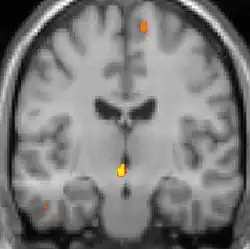

La tomographie par émission de positons (TEP) montre les zones du cerveau étant activées durant la douleur

Les images par tomographie à émission de positron indiquent les régions du cerveau qui sont activées lors de la douleur, par rapport aux périodes sans douleur. Elles montrent les régions du cerveau qui sont toujours actives durant la douleur en jaune/orange (appelé "matrice-douleur"). La zone au centre (dans les trois vues) est spécifiquement activée uniquement pendant la crise. Les photos sur la ligne du bas (effectuées par VBM) montrent les différences structurelles entre les patients souffrant d'AVF et des personnes saines : seulement une partie de l'hypothalamus est différente[50],[51].

Il semble exister des anomalies microstructurales hypothalamiques bilatérales (en l'occurrence l'existence d'une hypertrophie)[52] sans que l'on sache si ces anomalies sont la cause ou la conséquence de la répétition des crises.